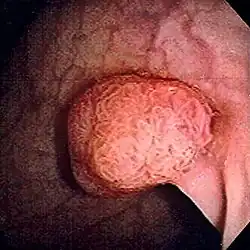

Polyp (Geschwulst)

Polypen sind makroskopisch sichtbare, meist gestielte Ausstülpungen der Mukosa (Schleimhaut).

Darmpolypen

Häufig treten Polypen als Adenome im Darm auf. Dort können sie im Rahmen einer Darmspiegelung mittels der Polypektomie entfernt werden, da die Gefahr einer Entwicklung zum Darmkrebs besteht (Adenom-Karzinom-Sequenz).